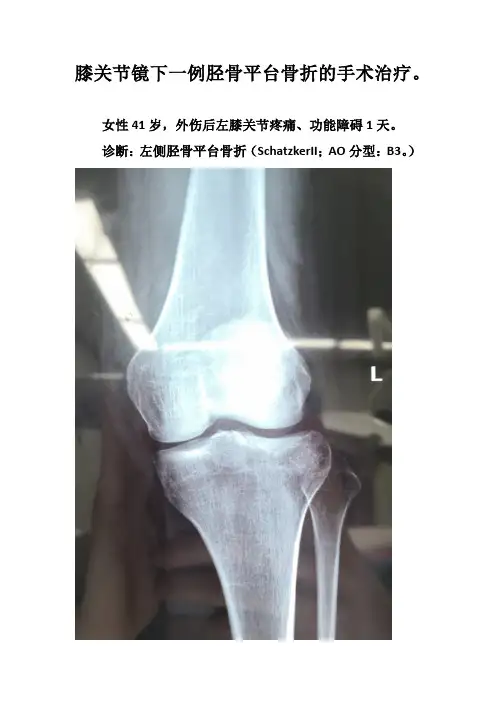

膝关节镜下一例胫骨平台骨折的手术治疗。

女性41岁,外伤后左膝关节疼痛、功能障碍1天。

诊断:左侧胫骨平台骨折(SchatzkerII;AO分型:B3。